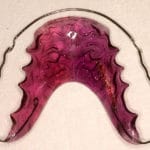

Pour les enfants et les jeunes plutôt des appareils amovibles, ainsi que des appareils fixes collés (pièces métalliques) pour aligner les dents. Ceux-ci peuvent être choisis en option transparentes.